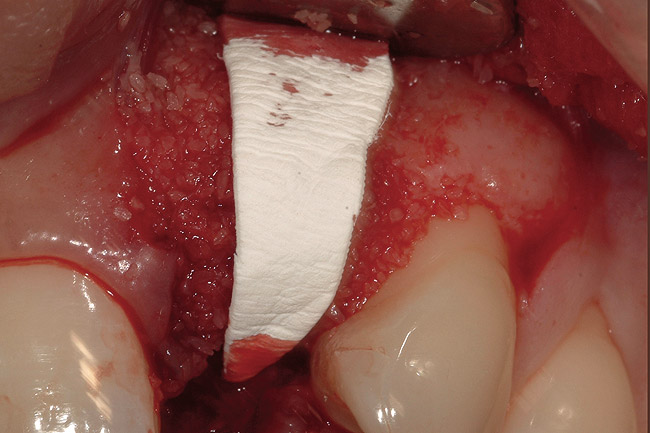

A 34-year-old woman presented with a chief complaint of mild discomfort and swelling associated with the maxillary left lateral incisor. The patient reported a history of root canal therapy and crown performed approximately 10 years earlier. Findings from the clinical examination revealed a localized buccal gingival swelling at the level of the mucogingival junction distal to the lateral incisor, with a 9-mm probing depth on the direct facial of the tooth (Figure 1 ). Observations from the radiographic examination demonstrated a periradicular radiolucency but suggested normal interdental bone levels (Figure 2 ). Surgical exposure following flap elevation exposed a 10-mm dehiscence defect of the buccal plate (Figure 3 ), which was consistent with a vertical root fracture and hopeless prognosis. The lateral incisor was extracted to minimize the loss of alveolar bone and this was followed by thorough degranulation of the socket. Particulate FDBA saturated with rhPDGF-BB for 10 minutes was then applied to augment the deficient ridge in preparation for future implant placement (Figure 4 ). The extraction site was developed to approximate the contours of the adjacent alveolar ridge. Then, a resorbable collagen membrane (Bio-Gide®, Osteohealth) was placed over the graft to facilitate graft containment and maintenance of desired alveolar contours (Figure 5 ). Placement of the membrane without disruption or displacement of the graft during completion of the surgical procedure and suturing is critical to ensure clot formation that will support bone formation.

Figure 4   Extraction socket and ridge defect augmented with particulate freeze-dried bone allograft (FDBA) saturated with rhPDGF.

Figure 4

Figure 5  Collagen membrane adapted to facilitate graft containment and maintenance of desired alveolar contours.

Figure 5